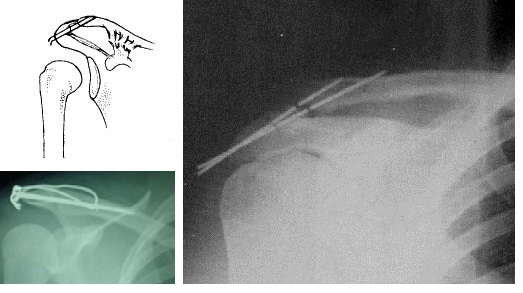

对于肩胛骨与锁骨之间,过去是用克氏针固定的,包括交叉克氏针和克氏针张力带,但是因为肩锁关节是半活动关节,常会因反复作用的剪切力造成克氏针断裂,而且断端有时特别难取出。